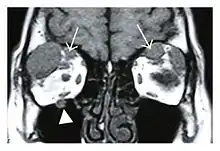

Right optic disc lesion in IgG4-ROD

Mass lesion around the right optic disc in a 44-year-old man with IgG4-related ophthalmic disease and a serum IgG4 of 599 mg/dL.[1] (T2-weighted MRI)